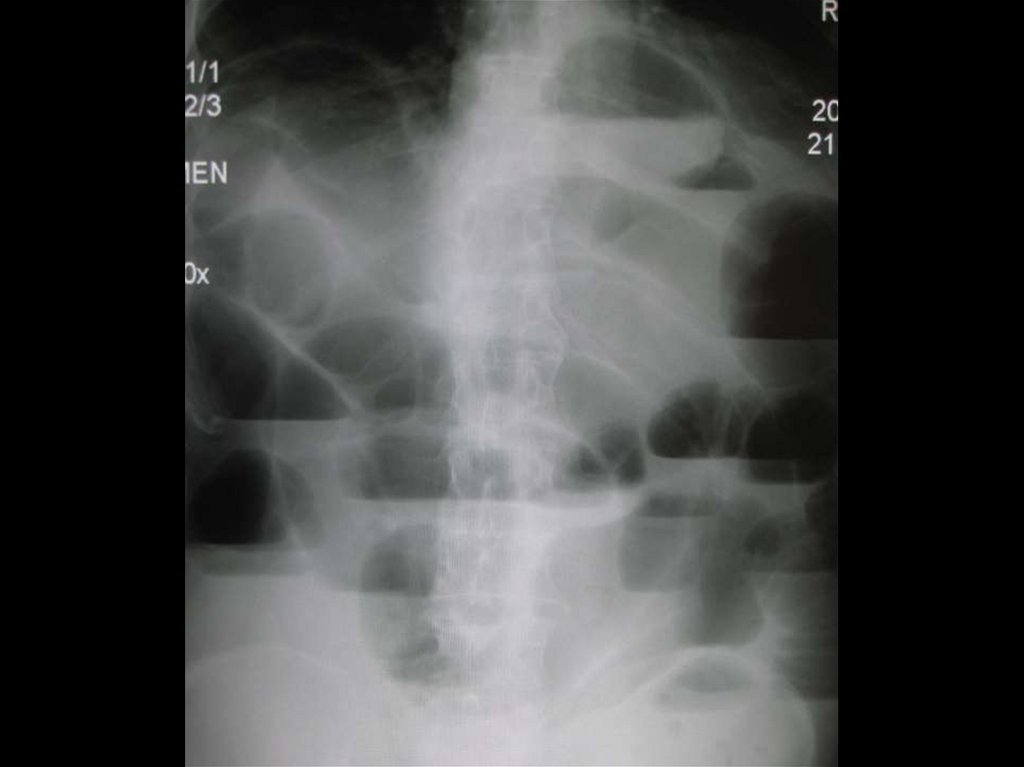

99. Механическая кишечная непроходимость.

МЕХАНИЧЕСКАЯ КИШЕЧНАЯ

НЕПРОХОДИМОСТЬ.

Обзорная рентгенограмма

брюшной полости.

Рентгенограмма после

перорального приема бариевой

взвеси.